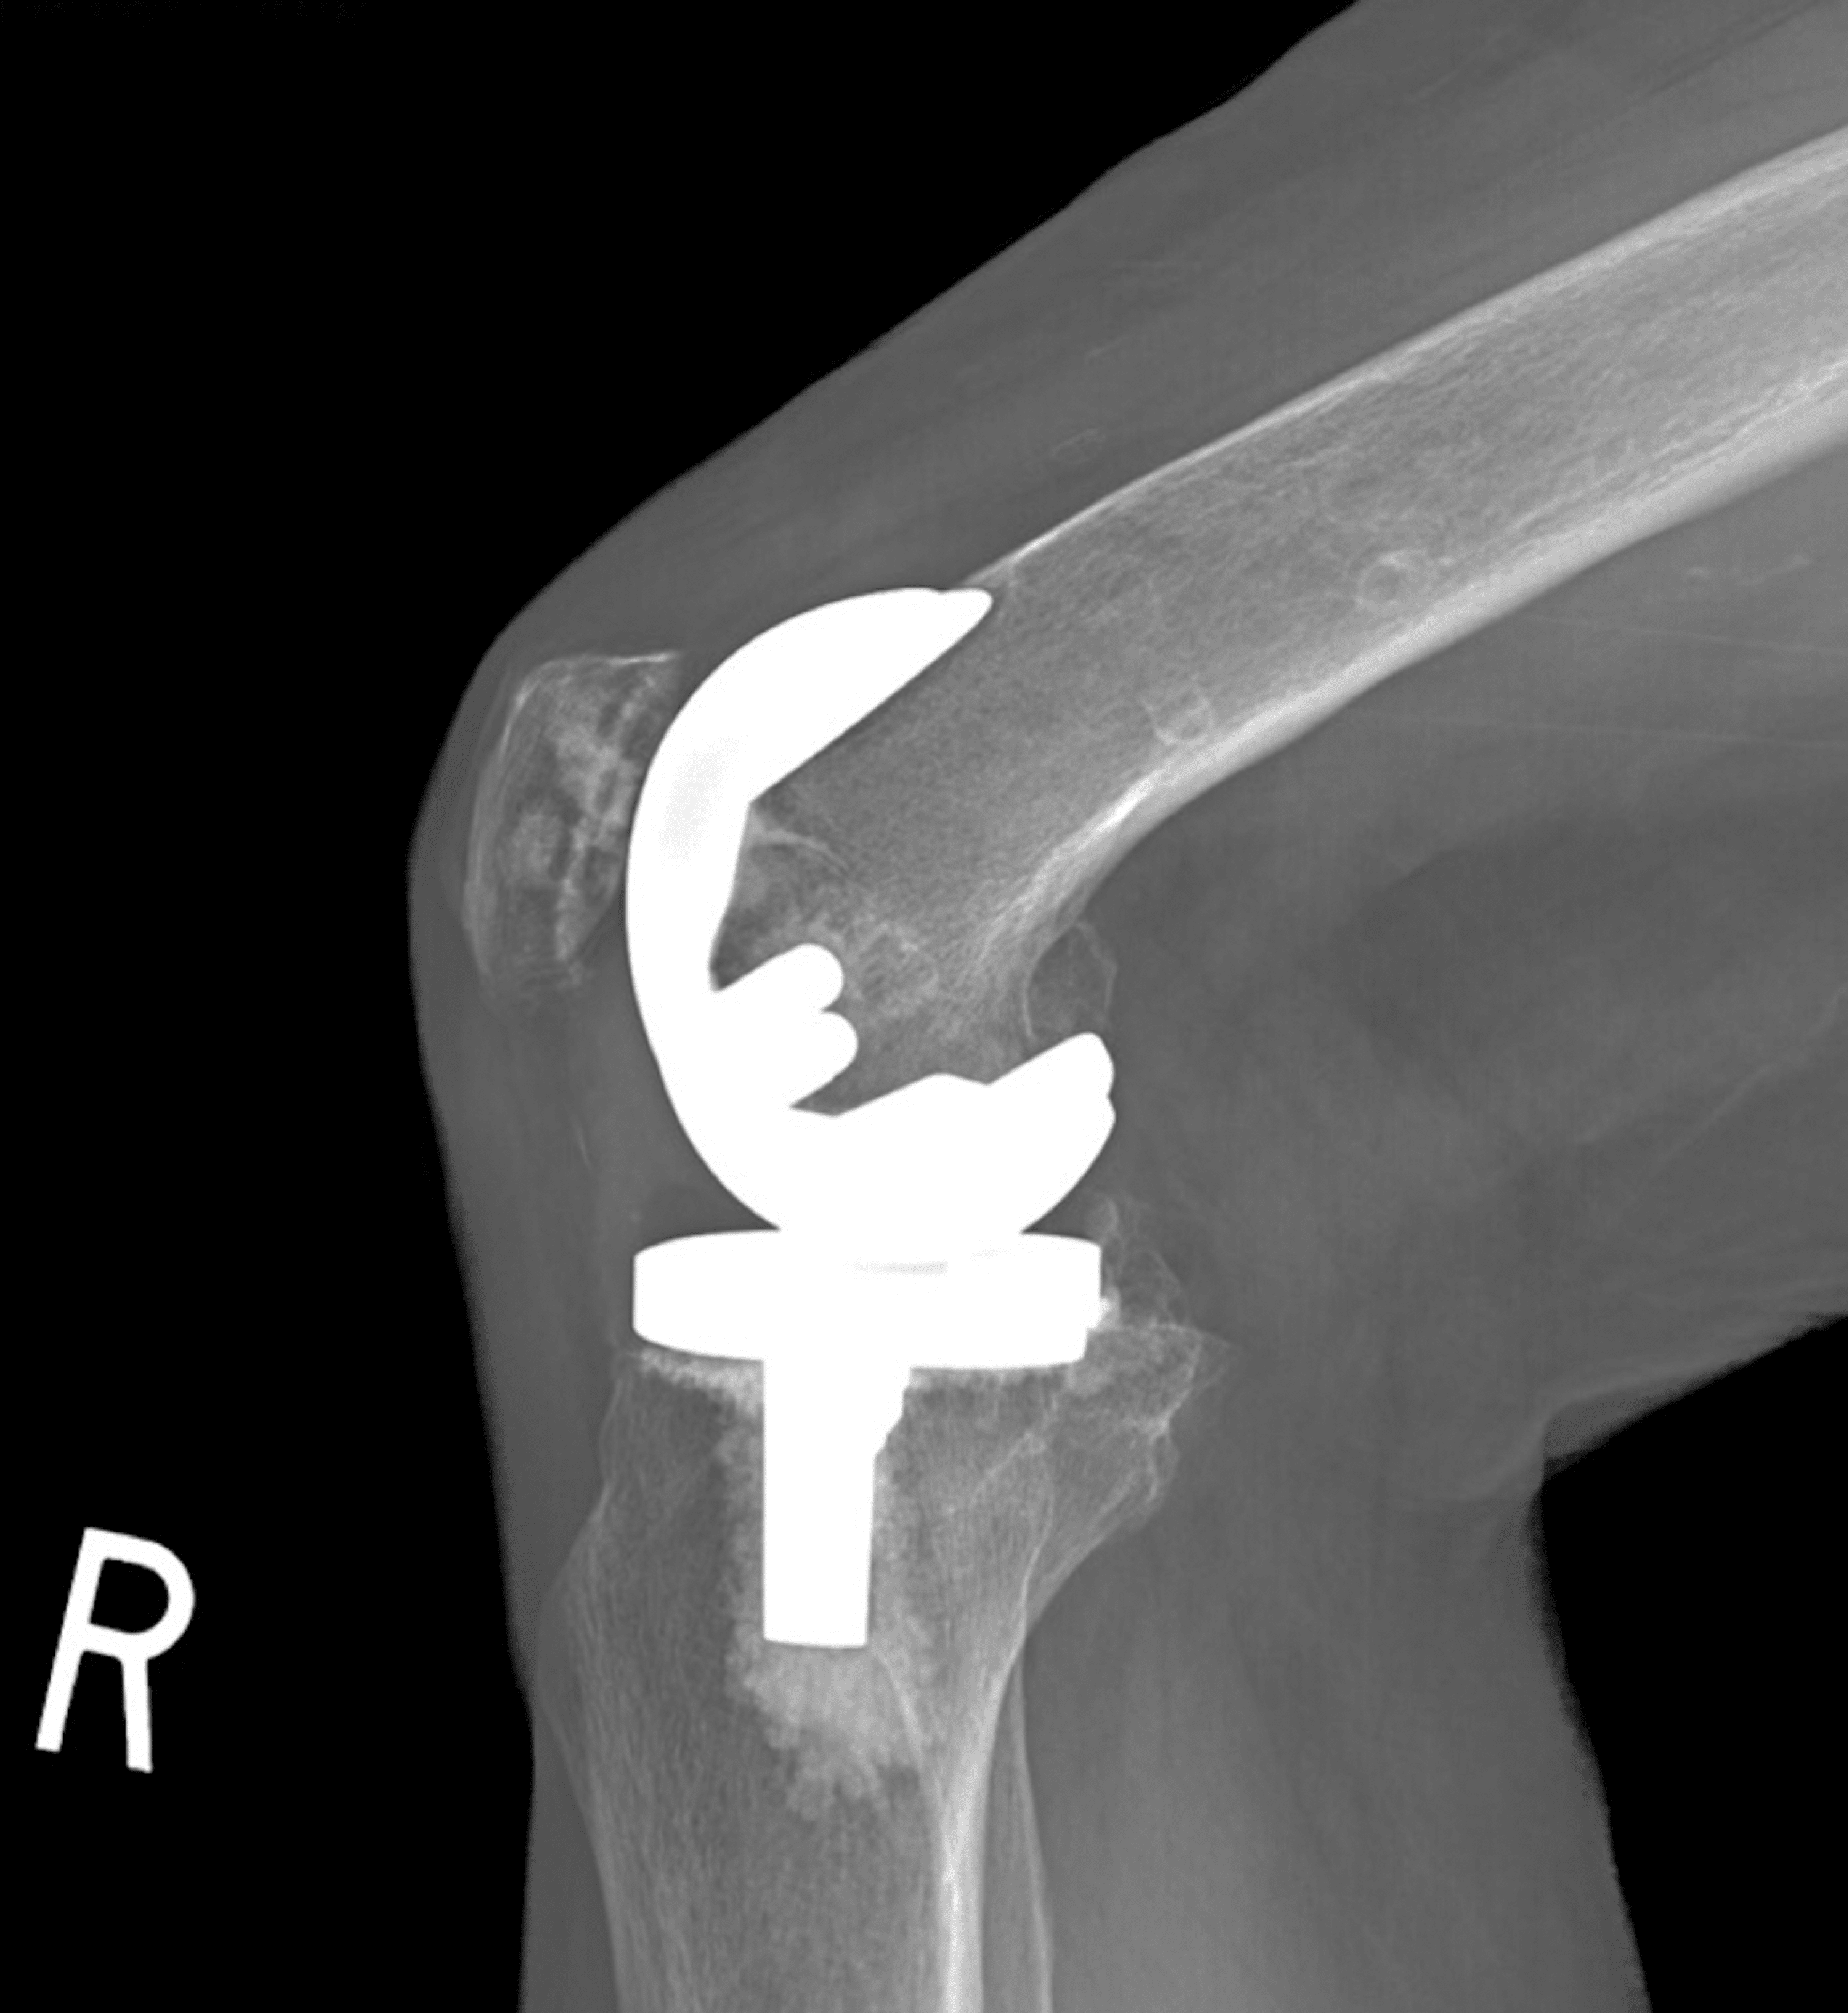

Medical Apparatus Imaging Guide fracture fixation Broken Screw In Shoulder Replacement with the increasing number of total shoulder replacements, periprosthetic (near the implant) fractures are more likely. This surgery replaces the damaged parts. shoulder fractures most often involve the clavicle (collarbone), proximal humerus (top of the upper arm bone), or the scapula (shoulder blade). if the fracture severely damaged your shoulder joint, you may need shoulder replacement surgery.. Broken Screw In Shoulder Replacement.